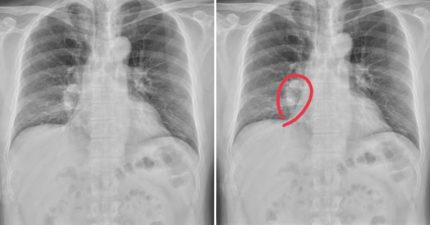

阿嬤餵孫吃整顆花生 1歲孫「肺部開始塌陷」醫氣炸:到底還要講幾次?

February 13, 2026

健康, 台灣, 知識